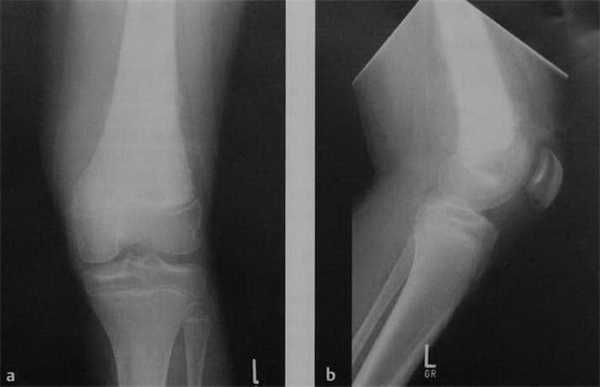

![Снимки МРТ и КТ. Остеосаркома]()

а, b Остеосаркома бедренной кости. Рентгенологическое исследование левой бедренной кости в двух проекциях. Мальчик 16 лет c остеосаркомой дистального отдела большеберцовой кости. Типичная агрессивная структура роста с распространенной реакцией надкостницы (шиповидная структура дает картину «лучей солнца»). Оссификация в окружающих мягких тканях.